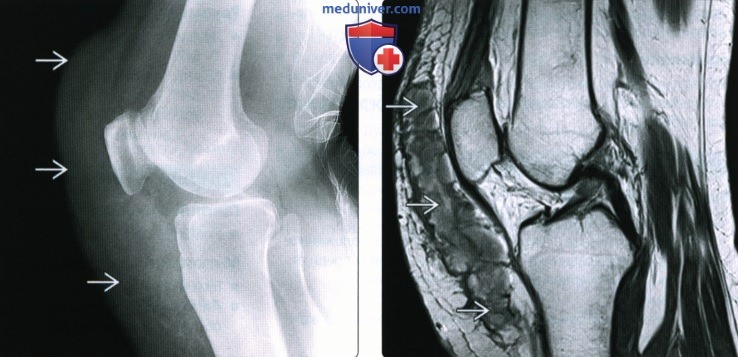

Заболевание сустава: симптомы и лечение